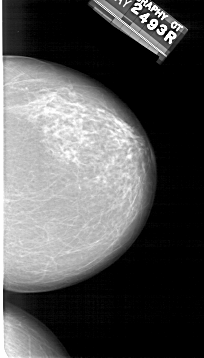

A_1410_1.RIGHT_MLO

RIGHT_MLO LINES 6316 PIXELS_PER_LINE 3286 BITS_PER_PIXEL 12 RESOLUTION 43.5 NON_OVERLAY